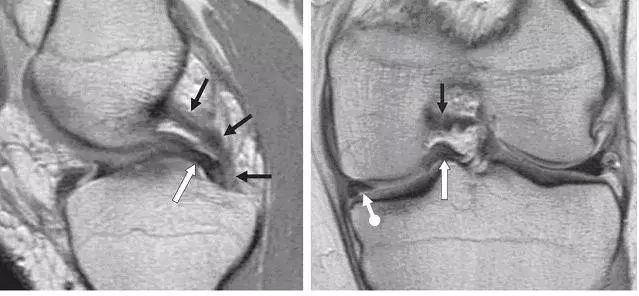

图 2 正常半月板

左图:外侧半月板,由于横截面面积一致,故在MRI 上可见外侧半月板前后角(纵向白色箭头)形状和大小较相似。上下腘肌半月板纤维束(黑色箭头)在外侧半月板后角处,形成裂孔,中间有腘肌腱(水平白色箭头)通过。右图:内侧半月板,可见后角(白色圆箭头),略大于前角(白色直箭头)